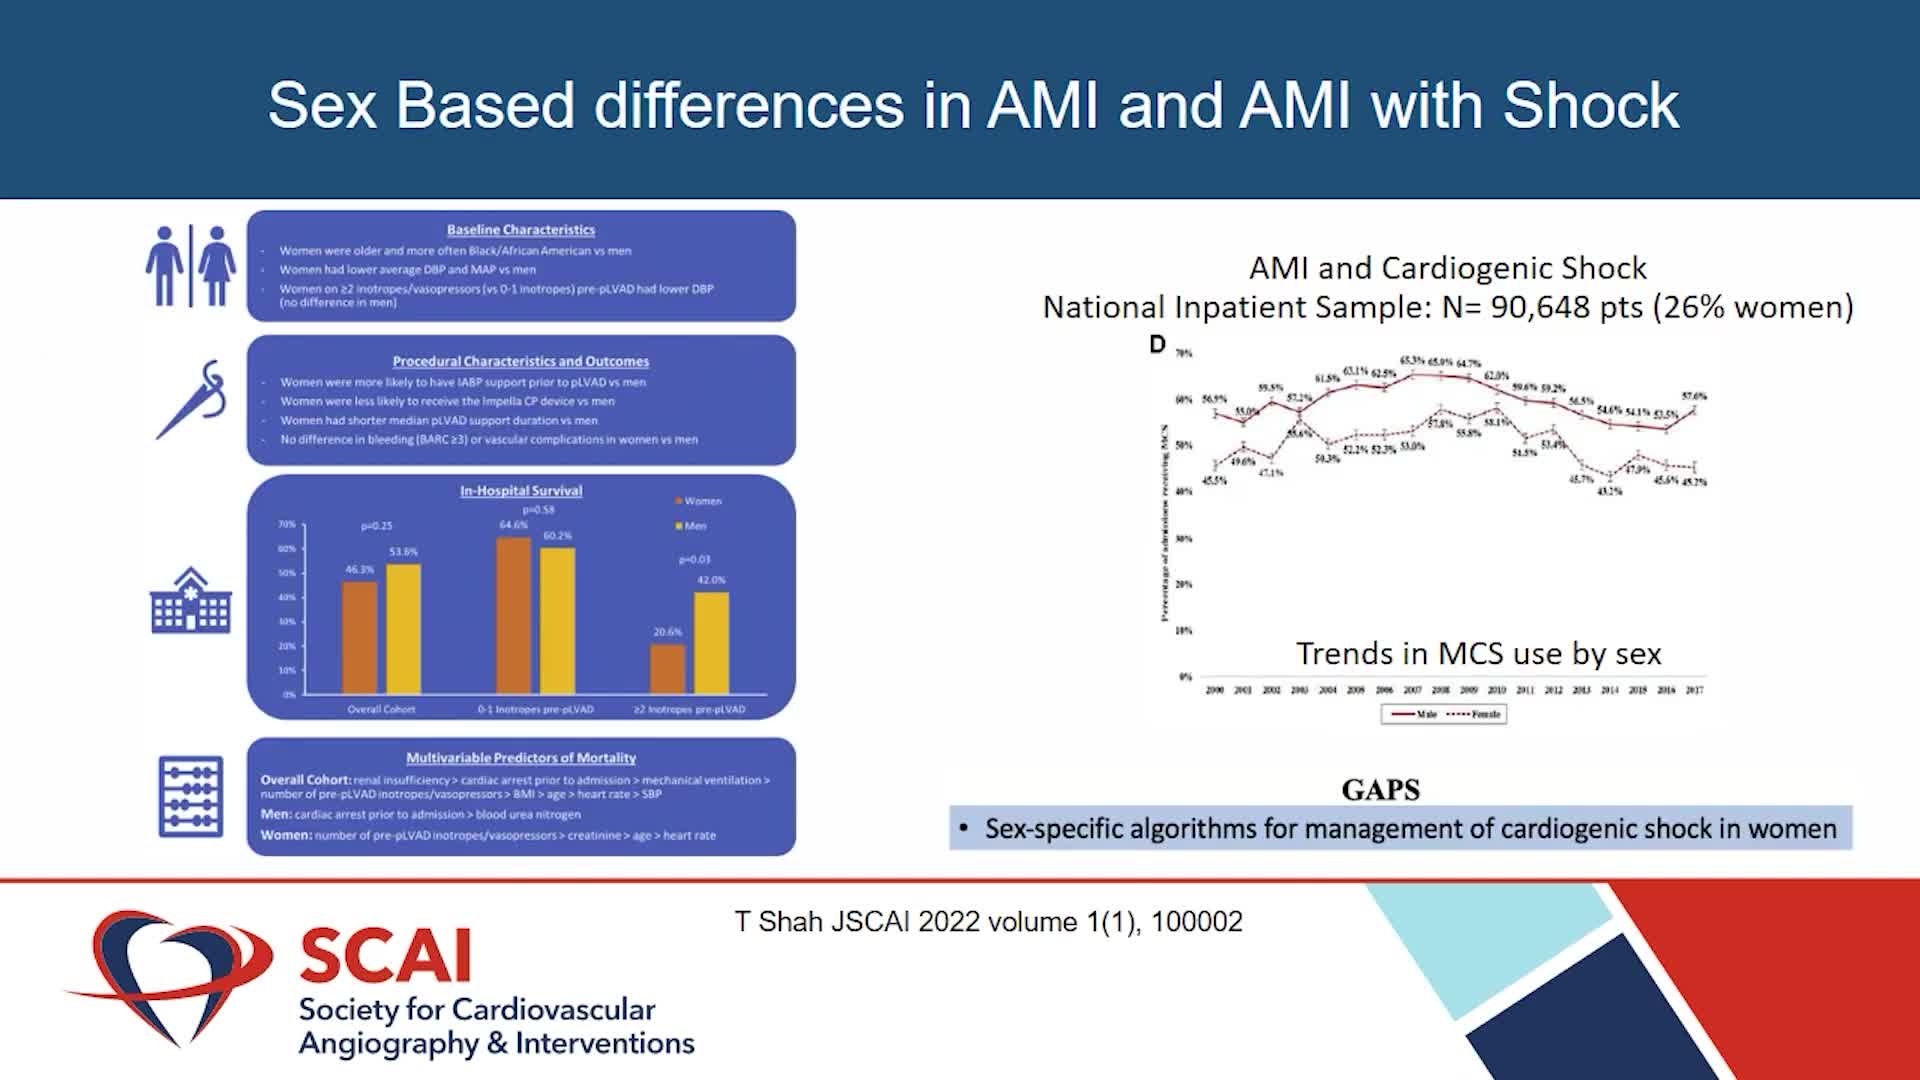

Simplify your procedures with Intravascular Lithotripsy (IVL) by safely modifying intimal and medial calcium to achieve optimal outcomes while minimising trauma, complications and costs due to its unique MOA.

Shockwave IVL Coronary Real-World Cases, Outcomes & Algorithms: An InCathLab Webinar